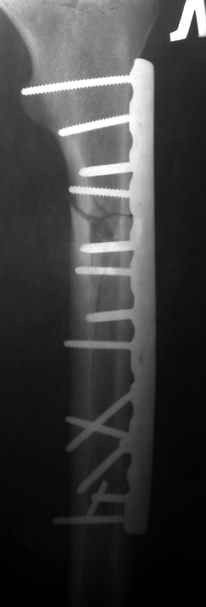

Больной 40лет, поступил 08.06.05г. с закр. оскольчатым переломом бедренной кости в с/3 и в/3 со смещ., 10.06.05г. выполнен остеосинтез LCP

,ч/з 3нед. после операции вскрыта нагноившаяся гематома, промывная система 1нед., через 3-и месяца пластина удалена в связи с инфекцией, секвестрэктомия, ЧКДО. АВФ 8мес.,периодически абсцедирование мягких тканей, санирующие операции, в настоящее время вскрыт абсцесс в с/3 бедра, м/ткани в обл. стержней инфицированы, полость абсцесса сообщается с проксим. и частью дист. стержней дальнейшая тактика?